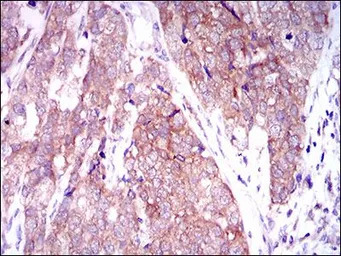

IHC-P analysis of bladder cancer tissue using GTX60648 Mark3 antibody [2G12].